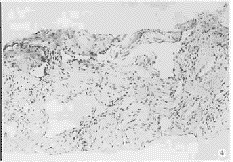

图3 肝右叶圆形高回声

图4 图3患者的病理组织学所见(HE染色,20×):在纤维结缔组织间见有较多的直径>0.40 mm的血窦,病理诊断:肝血管瘤